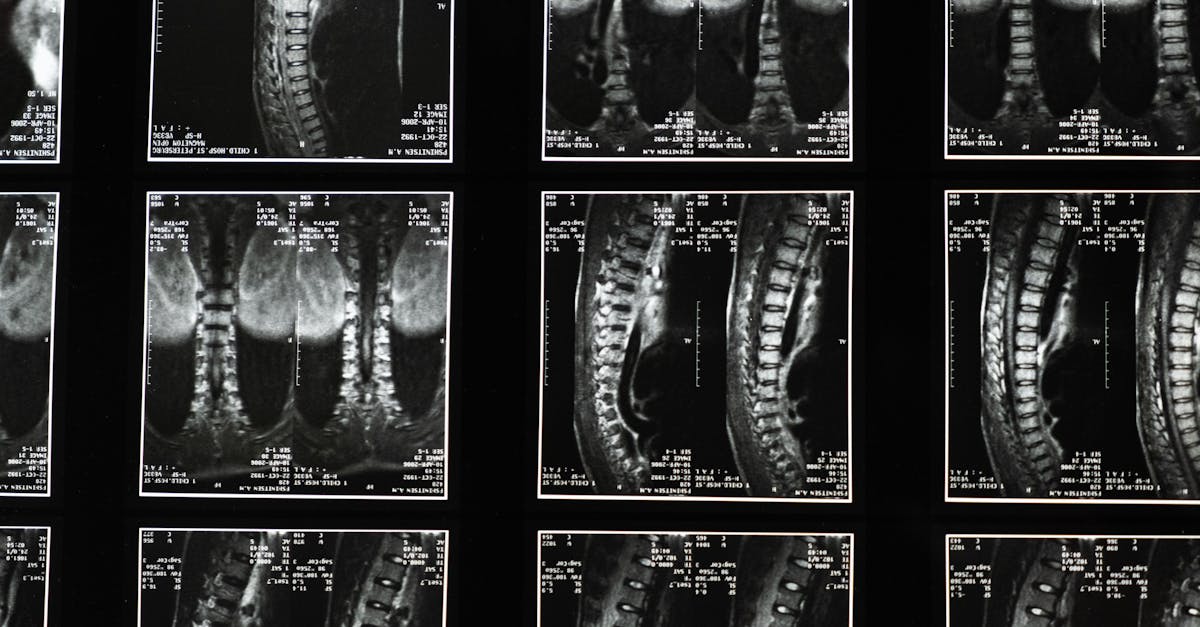

Avant de commencer un traitement de décompression neurovertébrale, il est crucial de procéder à une évaluation exhaustive de l’état de santé du patient. Cela inclut des examens d’imagerie tels que l’IRM ou la radiographie pour déterminer l’étendue de la sténose et toute autre condition sous-jacente. Une évaluation clinique minutieuse permet d’adapter le traitement à chaque patient, optimisant ainsi les chances de succès.